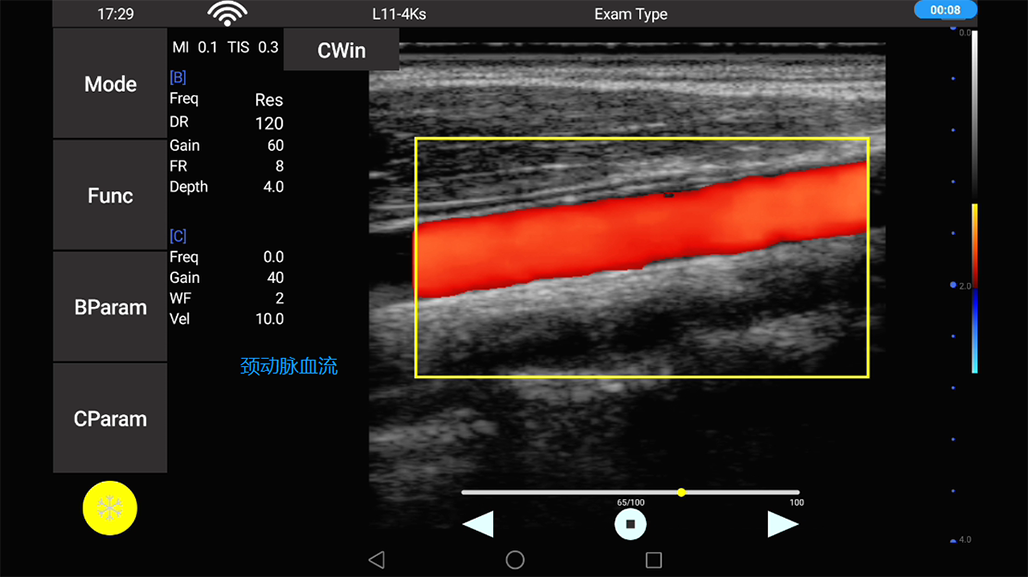

• 线阵

甲状腺

血管

神经

肌骨等